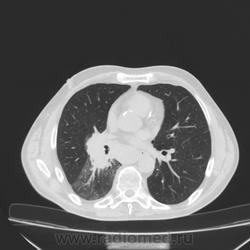

Состояние после торакопластики.

Молодой человек 30 лет, в 04 году выявлен фиброзно-кавернозный ТБ, в течение 12 месяцев лечился в стационаре, прооперирован-5реберная торакопластика справа, через 3 года переведен в 3ГДУ, в 10году снят с ДУ по излечению. Пришел провериться по ухудшению состояния. На КТ легких данных за рецидив ТБ, вроде нет. С " торакопластикой" был единственным пациентом на учете.

Состояние после правосторонней 5-реберной торакопластики по поводу ФКТ.Грубые остаточные изменения:поликистоз,буллезно-дистрофические изменения,плевропневмоцирроз правого легкого..Нет ли  мелкоочаговой диссеминации в обоих легких?Нужен Rархив.(ПТД).

Нет, это кальцинаты и более плотные уже. Архив только пленочный, 8 лет назад "цифры" не было. Можно и пленку перефотать...

Редко встречалось, а на КТ вижу впервые, спасибо за случай! На показанных изображениях отсевов не увидела.